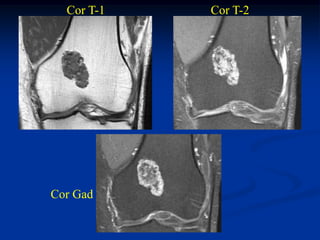

Cor T-1   Cor T-2

Cor Gad

Sag T-1   Sag T-2

Axial Gad

Axial T-2